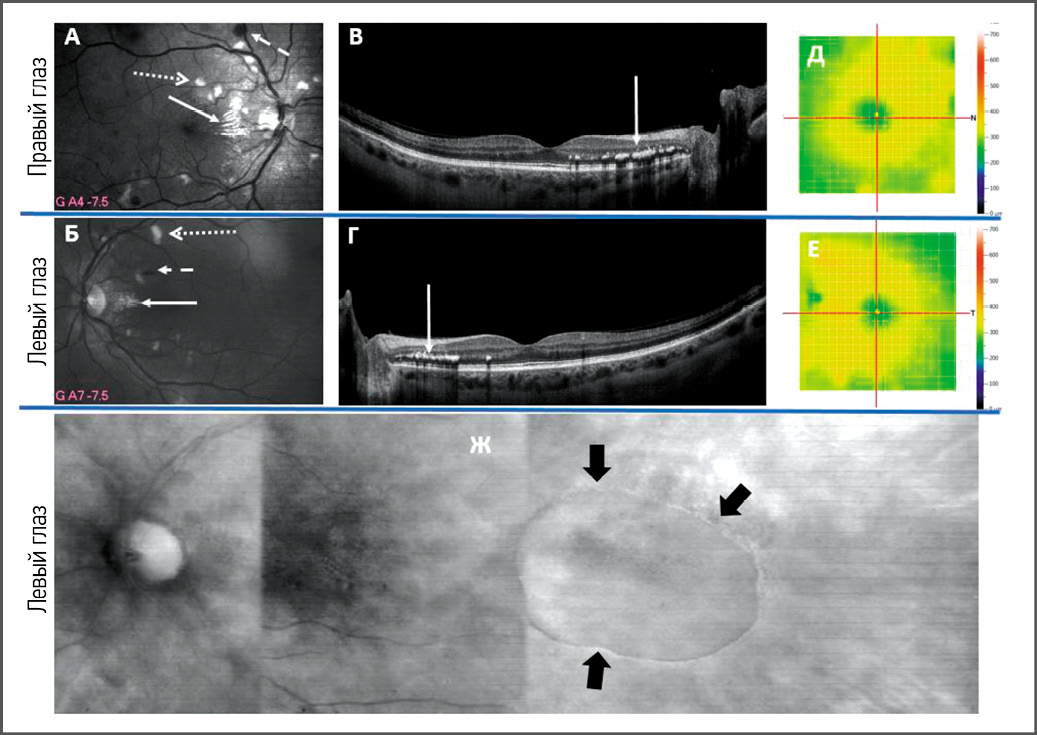

Комплексное лечение с достижением стойкой нормотензии позволяет значительно снизить выраженность ретинопатии. На рис. 2 и 3 показана динамика изменений глазного дна у пациентки со злокачественной АГ (по состоянию на 2014 год). Так, в 2014 году (см. рис. 2), по данным ОКТ (RTvue-100, Optovue, CША) и сканирующей лазерной офтальмоскопии в зелёном свете (F-10, Nidek, Япония), на обоих глазах в макулярной зоне наблюдалась картина гипертензивной нейроретинопатии: множественные «ватные» экссудаты (инфаркты слоя нервных волокон), интраретинальные кровоизлияния, твёрдые экссудаты (интраретинальные отложения липидов). На левом глазу, по данным сканирующей лазерной офтальмоскопии и ОКТ, была зафиксирована аккумуляция субретинальной жидкости с височной стороны от центра макулы, свидетельствовавшая о центральной серозной хориоретинопатии. При повторном осмотре в 2022 году (см. рис. 3) на фоне стойкой нормализации АД, по данным ОКТ (SOLIX, Optovue, CША) и фоторегистрации на фундус-камере Clarus 500 (Zeiss, Германия), а также при исследовании на сканирующем лазерном офтальмоскопе F-10 в зелёном и инфракрасном свете, визуализировался практически полный регресс исходных изменений глазного дна (твёрдые экссудаты, кровоизлияния резорбировались, «ватные» экссудаты разрешились). Таким образом, на основе современных методов визуализации удалось констатировать трансформацию картины ГР 3-й в картину ГР 2-й степени.

Рис. 2. Данные сканирующей лазерной офтальмоскопии в зелёном свете (А, Б), оптической когерентной томографии (В, Г), тепловой карты сетчатки (Д, Е), сканирующей лазерной офтальмоскопии в инфракрасном свете (ретро-режим, Ж) пациентки З. 53 лет со злокачественной артериальной гипертензией (исследование сетчатки выполнено в 2014 году). Примечание. На фрагментах А–Г видны твёрдые экссудаты (сплошная стрелка), на фрагментах А, Б – «ватные» очаги (точечно-пунктирная стрелка), интраретинальные кровоизлияния (штрихпунктирная стрелка); здесь же определяются суженные артериолы, расширенные венулы, АВС 1:3; артериовенозные перекрёсты 3-й стадии. На фрагментах Д, Е – утолщение сетчатки вследствие отёчности вблизи диска зрительного нерва. На фрагменте Ж стрелками ограничена зона серозной отслойки нейроэпителия сетчатки (признаки центральной серозной хориоретинопатии). Источник: ранее не опубликованные данные. / Fig. 2. Data from scanning laser ophthalmoscopy in green light (fragments A, B), optical coherence tomography (fragments C, D),thermal map of the retina (fragments E, F), scanning laser ophthalmoscopy in infrared light (retro mode, fragment G) in female Z., 53 years old, with malignant hypertension (retinal examination performed in 2014). Note. Fragments А–Г show solid exudates (continuous arrow), fragments А and Б show “cotton” foci (dotted-dotted arrow), intraretinal hemorrhages (dash-dotted arrow); narrowed arterioles, dilated venules, arteriovenous ratio (AVS) 1:3 are also determined here; arteriovenous crossings of the 3rd stage. Fragments Д, Е show thickening of the retina due to swelling near the optic nerve head. In fragment Ж, the arrows indicate the zone of serous detachment of the retinal neuroepithelium (signs of central serous chorioretinopathy). Source: previously unpublished data.